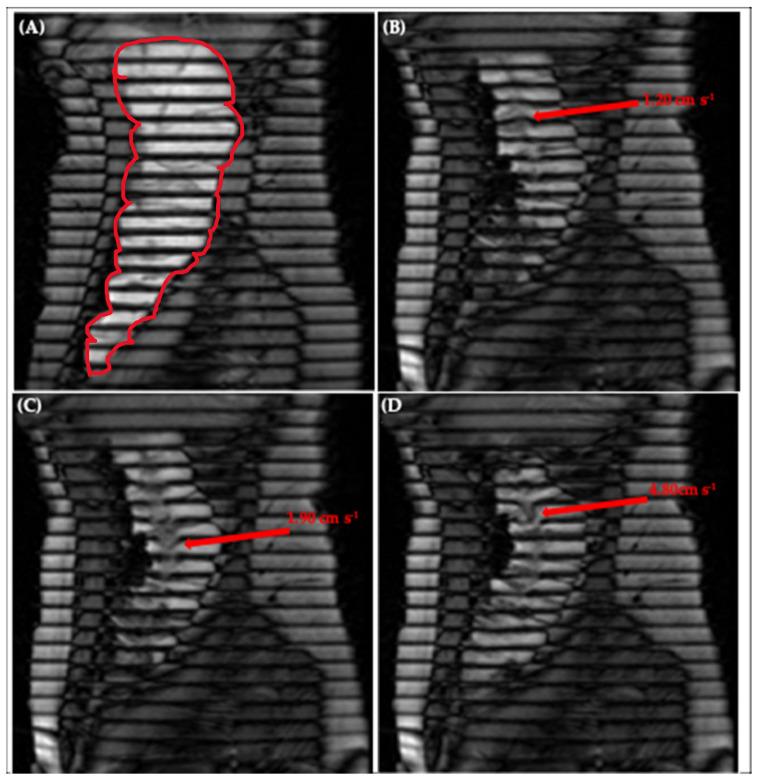

Knowledge of luminal flow inside the human colon remains elusive, despite its importance for the design of new colon-targeted drug delivery systems and physiologically relevant in silico models of dissolution mechanics within the colon. This study uses magnetic resonance imaging (MRI) techniques to visualise, measure and differentiate between different motility patterns within an anatomically representative in vitro dissolution model of the human ascending colon: the dynamic colon model (DCM). The segmented architecture and peristalsis-like contractile activity of the DCM generated flow profiles that were distinct from compendial dissolution apparatuses. MRI enabled different motility patterns to be classified by the degree of mixing-related motion using a new tagging method. Different media viscosities could also be differentiated, which is important for an understanding of colonic pathophysiology, the conditions that a colon-targeted dosage form may be subjected to and the effectiveness of treatments. The tagged MRI data showed that the DCM effectively mimicked wall motion, luminal flow patterns and the velocities of the contents of the human ascending colon. Accurate reproduction of in vivo hydrodynamics is an essential capability for a biorelevant mechanical model of the colon to make it suitable for in vitro data generation for in vitro in vivo evaluation (IVIVE) or in vitro in vivo correlation (IVIVC). This work illustrates how the DCM provides new insight into how motion of the colonic walls may control luminal hydrodynamics, driving erosion of a dosage form and subsequent drug release, compared to traditional pharmacopeial methods.